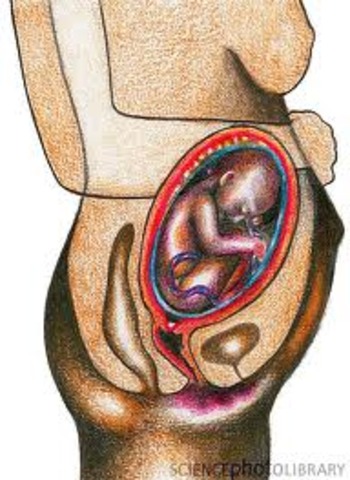

Prenatal Development

Moves into a head-down position.

• Month 9 - Baby

Month 9 - Baby

17-18 inches long and 5-6 pounds.

Weight gain continues until the week before birth.

Skin becomes smooth as fat deposits continue.

Movement decreases as the fetus has less room to move around.

Acquires disease-fighting antibodies from mothers blood.

Descends into pelvis, ready for birth.